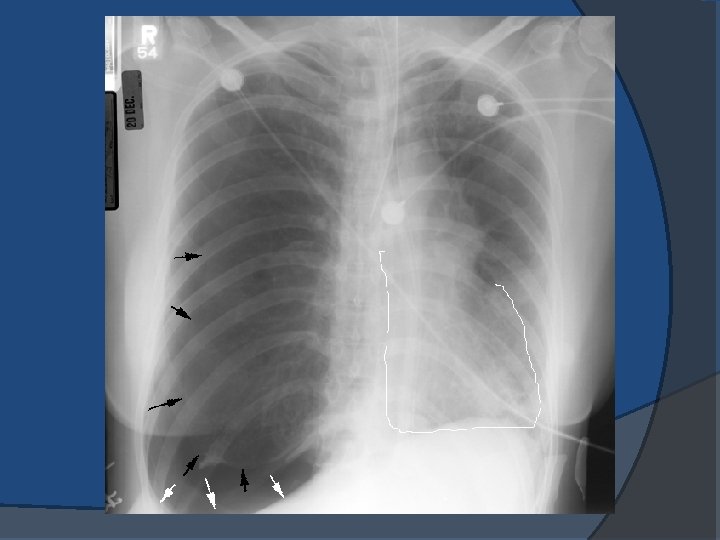

Barotrauma